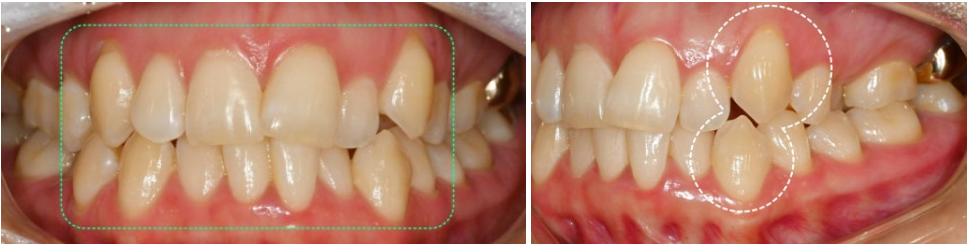

구강 내 모습을 보니

치아의 배열에서 덧니와 더불어,

여러 문제점이 관찰되었습니다.

양쪽 구치관계가 모두 2급 부정교합을 보였으며,

상악궁의 심한 협착이 두드러진 특징이었습니다.

입천장이 좁아지면서

아래 어금니들이 안쪽으로 기울어져 있었고,

특히 양쪽 두 번째 작은어금니가

입천장 쪽으로 위치하여

아래 치아와 반대로 교합되는 상황이었습니다.

위아래 전치부에는 심한 총생이 관찰되어

자연치들이 불규칙하게 배열되어 있었습니다.